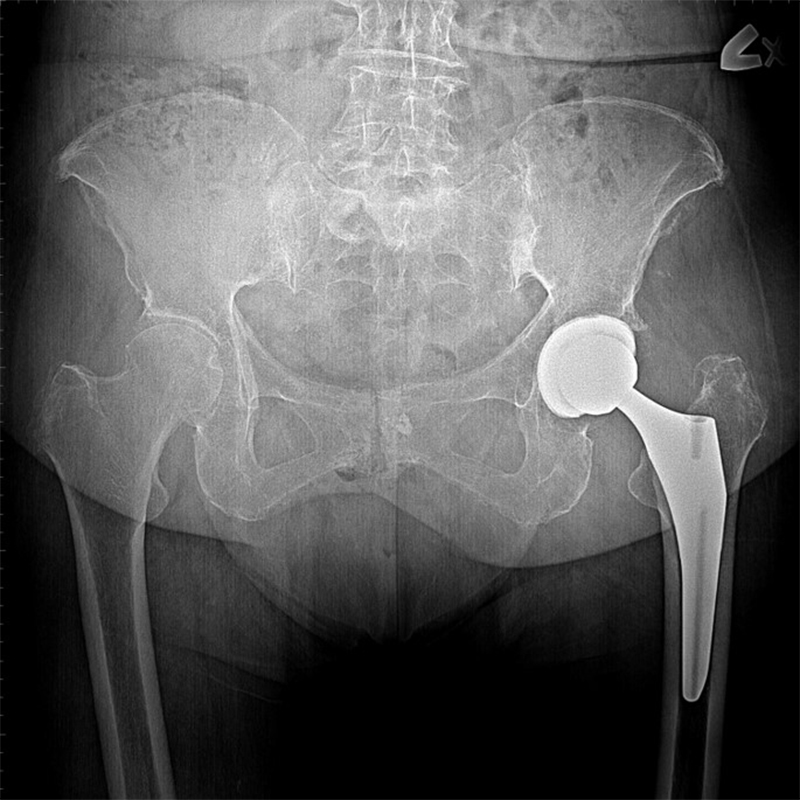

機器手臂手術 首頁 案例分享 髖關節手術 機器手臂手術 72歲 楊女士 退化性關節炎 術前 術後 60歲 彭先生骨股頭壞死 術前 術後 53歲 王女士退化性關節炎(DDH先天發育不全 CROWE TYPE 2) 術前 術後 83歲林女士退化性關節炎 術前 術後 83歲林女士退化性關節炎 術前 術後 楊女士 70歲 術前 術後 蔡女士 60歲 術前 術後